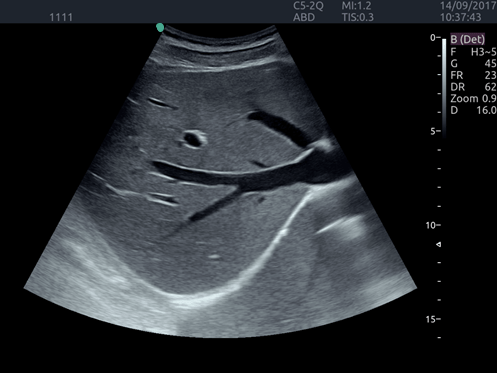

Invictus E5

O ultrassom Invictus E5 apresenta um design moderno e exclusivo, com perfeito fluxo de trabalho e interface intuitiva.

Dentre suas características inovadoras, podemos destacar a tela em LCD com rotação de 60° para ambos os lados, para otimização da visualização durante os exames; tela touch screen com menu totalmente customizável; painel de controle totalmente selado para facilitar limpeza e desinfecção da superfície, o que o torna referência para ser utilizado principalmente em Centro Cirúrgico.

Apresenta excelente qualidade de imagem, trabalho otimizado através de presets pré-determinados, sensibilidade e eficiência em aplicações de Point of Care e portanto, uma perfeita relação custo benefício.